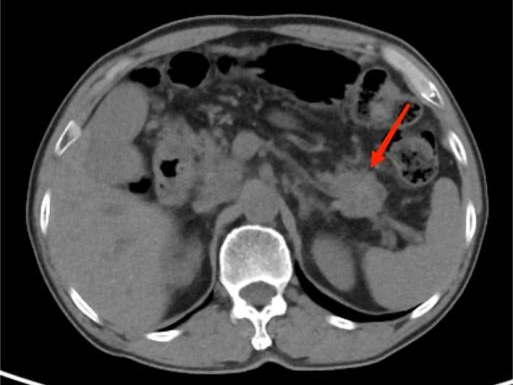

典型病例2:

男,73岁,无明显诱因出现皮肤、巩膜黄染,尿色加深,伴腹痛,为剑突下隐痛,向腰背部放射,伴腹胀、腹泻。图A:平扫CT示胰尾部肿块,密度不均。图B:增强扫描示病灶呈不均匀强化。图C:可见扩张的胆总管。